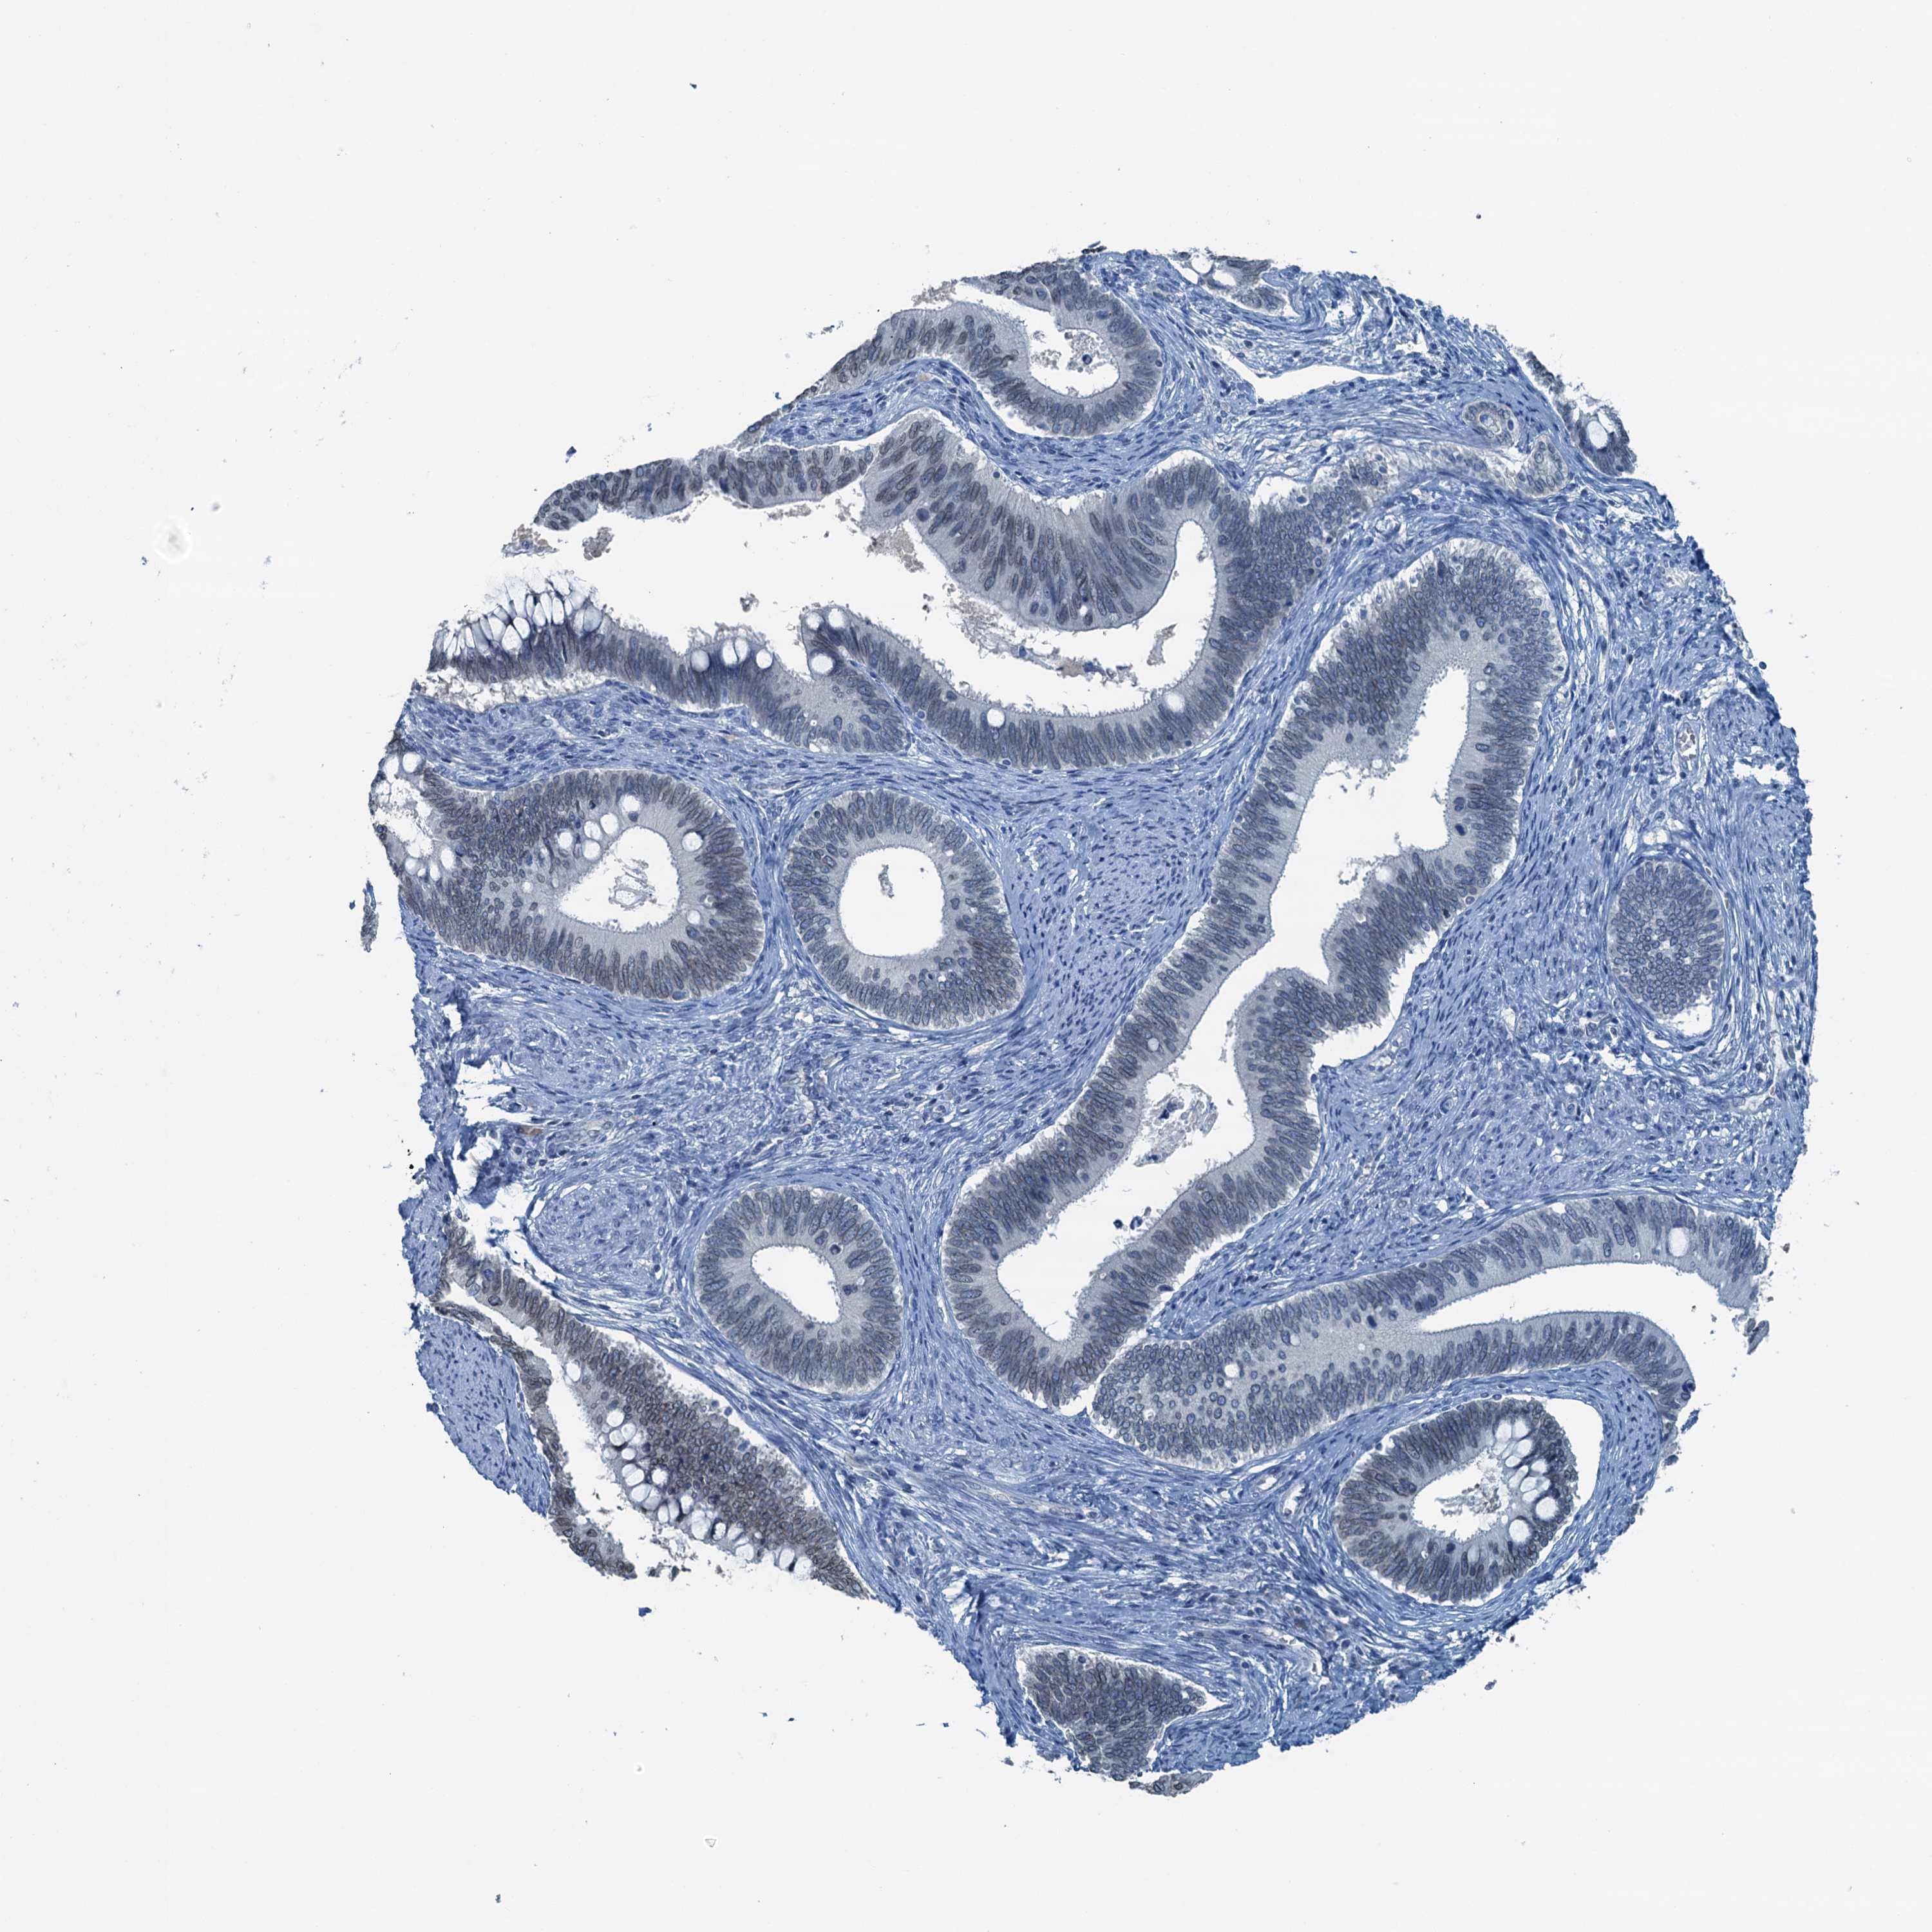

CERVICAL CANCER - Protein expressioni

A mouse-over function shows sample information and annotation data. Click on an image to view it in a full screen mode. Samples can be filtered based on level of antibody staining by selecting one or several of the following categories: high, medium, low and not detected. The assay and annotation is described here.

Note that samples used for immunohistochemistry by the Human Protein Atlas do not correspond to samples in the TCGA dataset.

Antibody stainingi

Antibody staining in the annotated cell types in the current human tissue is reported as not detected, low, medium, or high, based on conventional immunohistochemistry profiling in selected tissues. This score is based on the combination of the staining intensity and fraction of stained cells.

Each image is clickable and will lead to virtual microscopy that enables deeper exploration of all samples and also displays staining intensity scores, fraction scores and subcellular localization as well as patient and tissue information for each sample.

Antibody HPA040511

Staining

High

Medium

Low

Not detected

Intensity

Strong

Moderate

Weak

Negative

Quantity

>75%

75%-25%

<25%

None

Location

Nuclear

Cytoplasmic/membranous

Cytoplasmic/membranous,nuclear

Squamous cell carcinoma, NOS

Adenocarcinoma, NOS